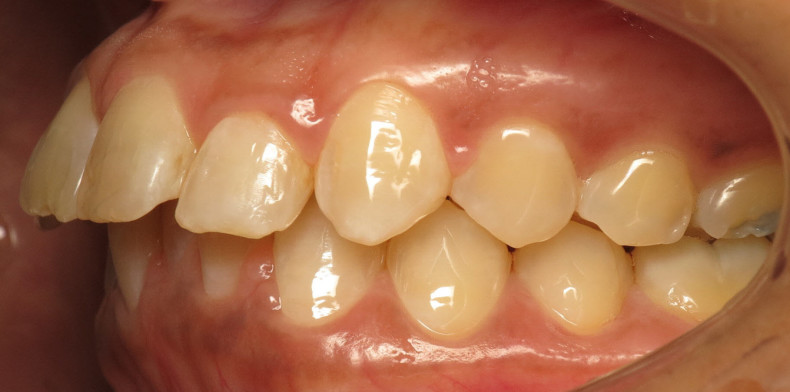

Der intraorale Befund (Abb. 2a–e) sowie die Modellanalyse (Abb. 3a–e) zeigten neben dem Diastema mediale im Oberkiefer vor allen Dingen eine Anteinklination und Supraokklusion beider Fronten. Besonders anterior wiesen beide Zahnbögen eine transversale Enge auf. Dies zeigte sich in einem deutlichen Unterkieferfrontengstand mit Labialkippung des Zahnes 41. Neben Abrasionen und Schlifffacetten, vor allem in der Front, waren auch vereinzelt Gingivarezessionen erkennbar. An Zahn 11 lag eine Schmelzfraktur der Inzisalkante vor. Durch die zwangsgeführte Laterognathie ergab sich eine Mittellinienverschiebung nach rechts von 3 mm. Eine beidseitige Distalokklusion bei vergrößerter sagittaler (6 mm) und vertikaler (5 mm) Stufe war erkennbar. Aufgrund der deutlichen transversalen Zahnbogenenge im Unterkiefer ergab sich links eine Tendenz zum Scherenbiss.